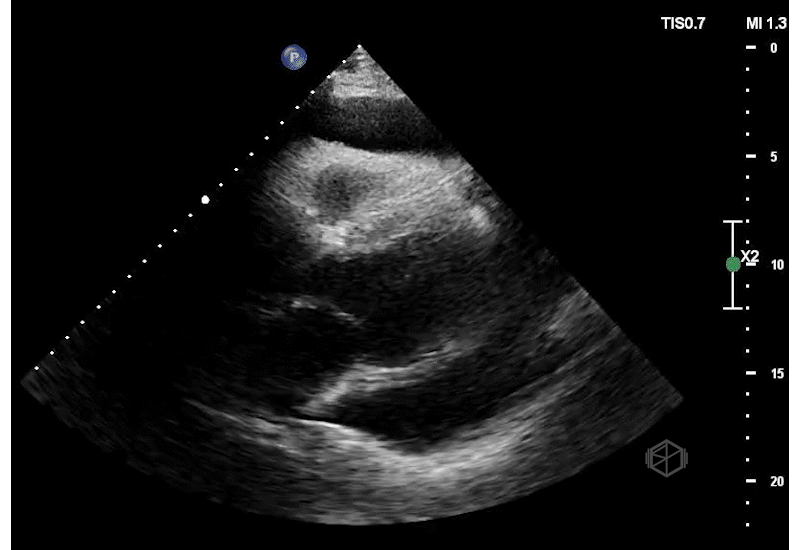

They did a POCUS echo and saw the following —

Not just rapid atrial fibrillation!

This is a massive pericardial effusion, measuring up to 5.0cm in it’s largest portion. There are signs of tamponade on this echo — aside from the obvious “swinging heart,” there is right ventricular diastolic collapse. The right ventricle does not get a chance to fully fill during diastole due to the extra-cardiac pressure from the pericardial effusion.

Diagnosis: Extra-large pericardial effusion with a side of tamponade

The patient had 1500ml of serosanguinous fluid drained by cardiology.